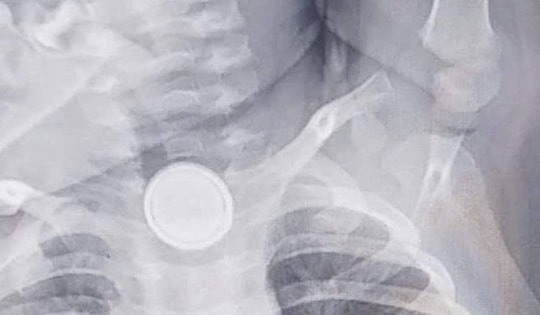

Điều dưỡng Nguyễn Thùy Trang bị thương nặng nhất với nhiều thương ở vùng mặt, cổ, ngực và lưng, trong đó có 2 vết thương thấu phổi, làm đứt tĩnh mạch cảnh ngoài và nhánh động mạch dưới đòn phải.